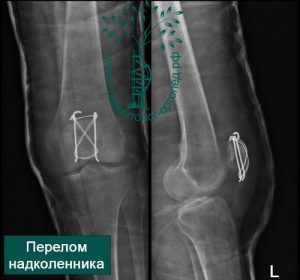

Остеосинтез коленного сустава

Остеосинтез коленного сустава 103 фотографий